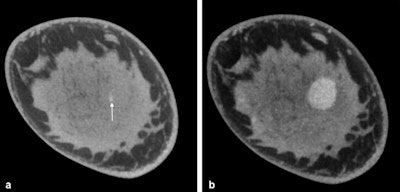

Top: Cone-beam breast CT, noncontrast-enhanced examination. Invasive ductal breast carcinoma is visible on the left. A: Digital mammography on the left in MLO projection. B: Breast CT, sagittal single layer with breast carcinoma (arrow) in the caudal breast sections. C: Coronal single slice with depiction of the tumor within the dense glandular breast tissue. Bottom: Cone-beam breast CT, noncontrast-enhanced examination. Mucinous breast carcinoma on the left. A: Sagittal single slice. B: Maximum intensity projection (MIP) of the dataset with breast carcinoma in the caudal breast sections. C: Reconstructed image with depiction of the surfaces of the intramammary structures and the tumor (arrow).For her pilot study, Wienbeck examined more than 100 female patients by means of cone-beam breast CT, including both women with malignant cancer as well as those with benign findings.